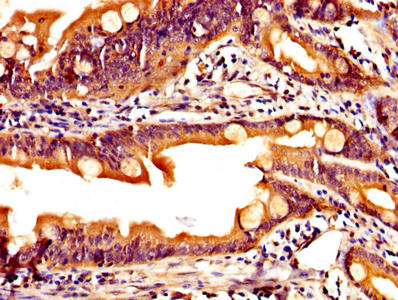

IHC image of CSB-PA12214A0Rb diluted at 1:200 and staining in paraffin-embedded human colon cancer performed on a Leica BondTM system. After dewaxing and hydration, antigen retrieval was mediated by high pressure in a citrate buffer (pH 6.0). Section was blocked with 10% normal goat serum 30min at RT. Then primary antibody (1% BSA) was incubated at 4°C overnight. The primary is detected by a biotinylated secondary antibody and visualized using an HRP conjugated SP system.